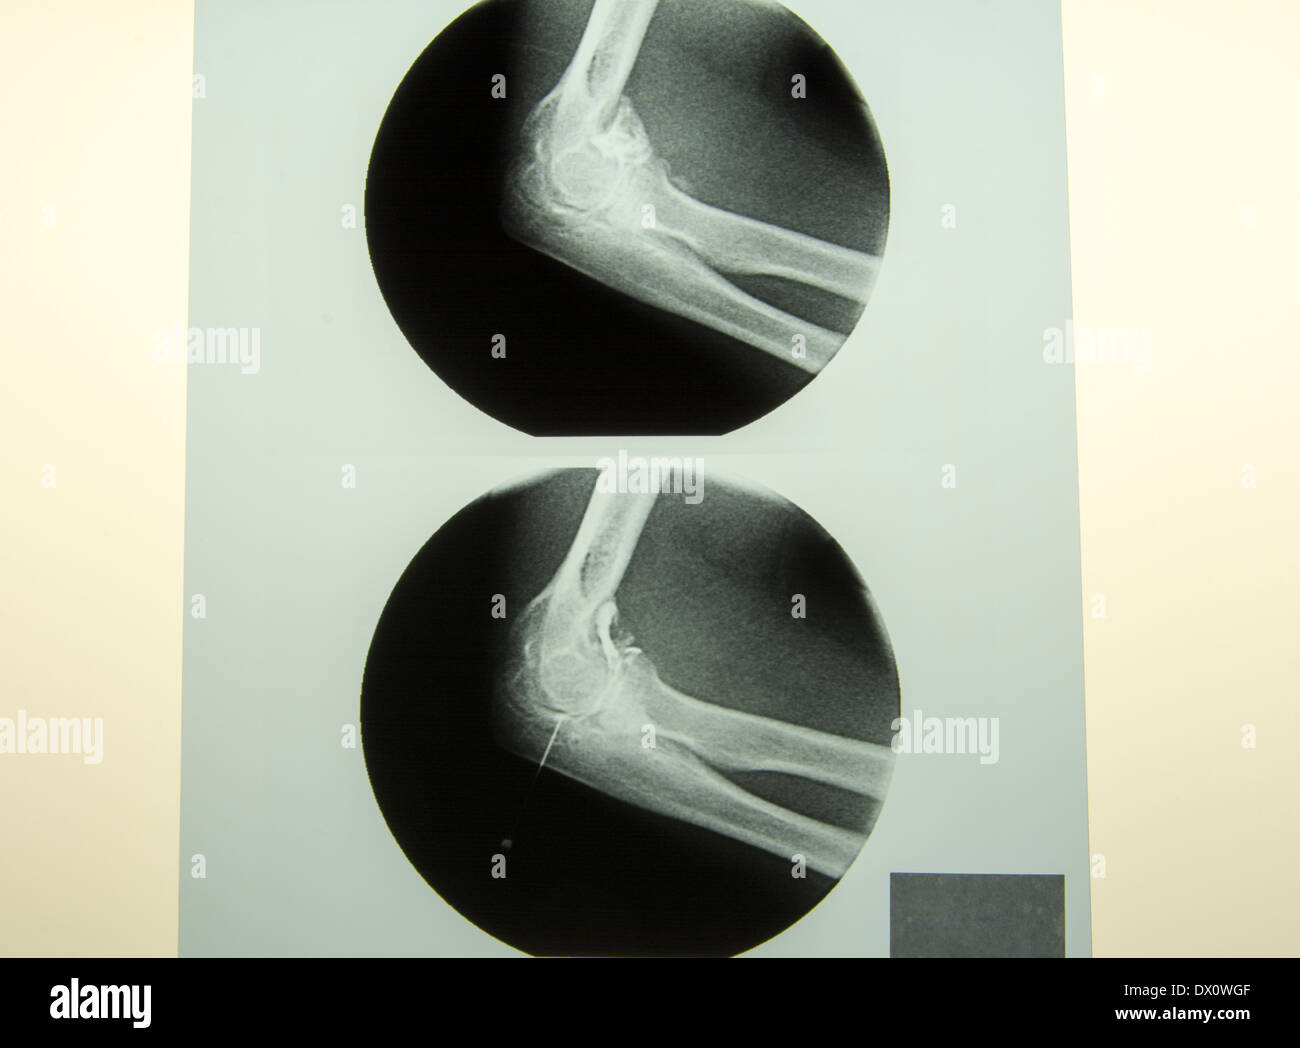

Needle In Foot Xray Two Views Needle On Xray If a sharp foreign body such as a needle enters the skin perpendicularly, the incision may miss the foreign body if parallel to. Of the more than 6 million who. On radiography, the needle appeared opaque ( fig. Metallic objects such as needles or elongated objects such as fish bones, chicken bones, and toothpicks are the foreign bodies most frequently. Needle On Xray.